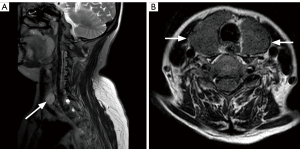

Of the 1,313 patients, 98 patients (7.5%) had incidental thyroid abnormalities on cervical spine MRI scans. Of the thyroid abnormalities, 76 patients (77.6%) were female and 22 patients (22.4%) were male, showing a female predominance in the incidence of thyroid abnormalities. Compared to group A, group B showed a significantly higher proportion of females (P=0.007). The most common thyroid abnormality was thyroid nodules (69/1,313, 5.3%), followed by goiters (18/1,313, 1.4%), Hashimoto thyroiditis (5/1,313, 0.4%), and thyroid cancer (6/1,313, 0.5%; Figure 2).

Among patients younger than 35 years old, 2 patients had incidental thyroid abnormalities larger than 10 mm. Of the patients older than 35 years old, 20 patients had thyroid nodules larger than 15 mm. In addition to the 18 patients with goiters. Forty patients older than 35 years were recommended to undergo further US examination based on the ACR criteria (Table 3). Of the 98 patients with thyroid abnormalities, US was performed in 27 patients. Among these 27 patients, 22 met the ACR criteria, and 5 did not meet the ACR criteria but still completed the US examination. In addition, 5 patients were diagnosed with Hashimoto thyroiditis by US and hematologic indices. The other 6 cases of thyroid cancers were diagnosed with postoperative pathology. None of the patients had suspicious features found in the thyroid region.